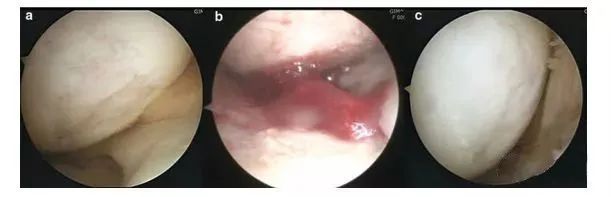

人类的膝关节结构、功能复杂,对于人体来说,膝盖是个十分“微妙”的存在,多用容易磨损,用得太少又容易“生锈”。无论对于运动员,或者是普通人,关节都是最容易在运动中被损伤的组织器官之一。 01 越来越薄的软骨 作为现代人的通病,以膝关节为例,青春期软骨厚度通常为2.5公分,而55岁以后常只剩下0.5公分,甚至更薄而产生破裂、骨刺,这种损伤常常不可逆,带来长期的巨大痛苦。据世界卫生组织提供的数据,50岁以上人群的骨关节病发生率为50%,70岁的老年人发病率高达80%。 现在,很多研究者都在探寻修复关节软骨损伤的方法,目前看来,保护膝盖、预防损伤依然是最好的解决方式。但对于关节损伤的常规治疗方法非常保守:无非通过保护延缓病变进程,或者直接接受关节置换手术而已。 所以一直有很多研究者都在探寻修复关节软骨损伤的方法,例如用干细胞促进组织修复,这些方法也逐渐展现出较为乐观的应用前景。 02 干细胞修复软骨 墨尔本干细胞治疗中心利用患者自身的间充质干细胞注入膝关节治疗膝关节损伤的临床研究是全球范围都较为知名的一项临床试验,这个试验共涉及70名患者,分为30名一组进行对照。最终结果显示,大部分参与试验的患者膝关节功能有了很大的改善:三分之二的患者膝盖疼痛程度和活动受限程度减少了一半,并且保持了一年以上。 术后第二次关节镜检查(图a)。在所有4名患者中,移植区域具有保存完好的透明状软骨结构。4例活检标本的组织学检查结果表明,与邻近关节炎软骨相比,修复效果更好。组织显示存在软骨细胞样细胞,以及透明软骨样结构和基质。所有四个活检标本均为无异位钙化和血管化。并且没有发现炎症迹象。 上图a为治疗前关节镜检查结果,可以看出软骨存在缺损。图b为脂肪间充质干细胞联合PRP治疗,图c为治疗后结果,软骨得到了修复。 在一部来自Youtube上的视频中,医生采集患者自身外周血中的干细胞,联合PRP(富血小板血浆)治疗关节病,患者自述这种疗法有效缓解了疼痛,提高了生活质量。